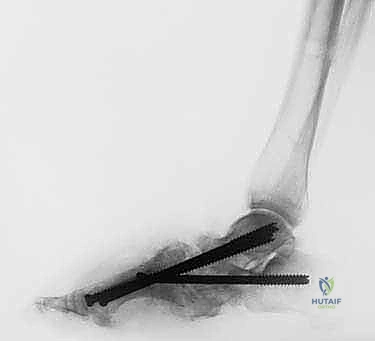

4. المرحلة الثانية: دمج المفاصل (Joint Arthrodesis)

بمجرد أن تصبح العظام في الوضع الصحيح بفضل التثبيت الخارجي، ننتقل إلى مرحلة التثبيت الدائم.

* من خلال شقوق جراحية صغيرة جداً (Minimally Invasive)، يقوم الدكتور هطيف بإزالة الغضاريف التالفة من المفاصل المستهدفة (غالباً مفاصل منتصف القدم والكاحل).

* يتم استخدام تقنيات متقدمة لتحفيز العظام على الاندماج (مثل استخدام طعوم عظمية أو بروتينات محفزة لنمو العظم).

* يتم ضغط العظام معاً باستخدام جهاز التثبيت الخارجي نفسه لضمان التحامها كعظمة واحدة صلبة.

5. مرحلة التصلب والشفاء (Consolidation Phase)

يبقى جهاز التثبيت الخارجي في مكانه لعدة أشهر (عادة من 3 إلى 6 أشهر) حتى تندمج العظام تماماً وتصبح قادرة على تحمل وزن الجسم. الميزة الكبرى هنا هي أن المريض يمكنه (بناءً على توجيهات الطبيب) البدء في تحميل الوزن جزئياً على القدم المصابة، لأن الإطار الخارجي هو الذي يتحمل العبء الميكانيكي وليس العظام الهشة.